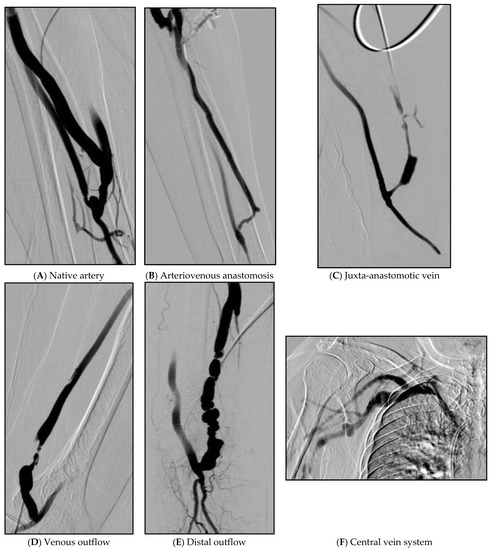

| Degree of stenosis | ||

| Stenosis | 90–100% | 35 (43.7) |

| 75–89% | 19 (23.8) | |

| 50–74% | 26 (32.5) | |

| Number of lesions | 1 site | 42 (52.5) |

| 2 sites | 28 (35.0) | |

| ≥3 sites | 10 (12.5) | |

| Location of lesions | Native artery | 11 (13.8) |

| Arteriovenous anastomosis | 15 (18.8) | |

| Juxta-anastomotic vein | 53 (66.3) | |

| Venous outflow | 32 (40.0) | |

| Distal outflow | 17 (21.3) | |

| Central venous system | 2 (2.5) |